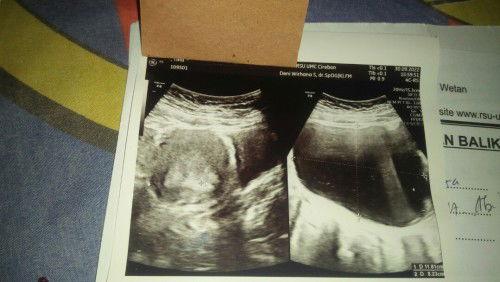

30 September 2022 Qodarullah.. keguguran di UK 11W, penyebabnya karena ada Kista,dan udh besar 11cm.. Insyaallah 3 Oktober 2022 Operasi pengangkatan Kista,dan pembersihan rahim (kiret) Minta Do'a nya bunda2,terimakasih..

Hamil 11W Keguguran